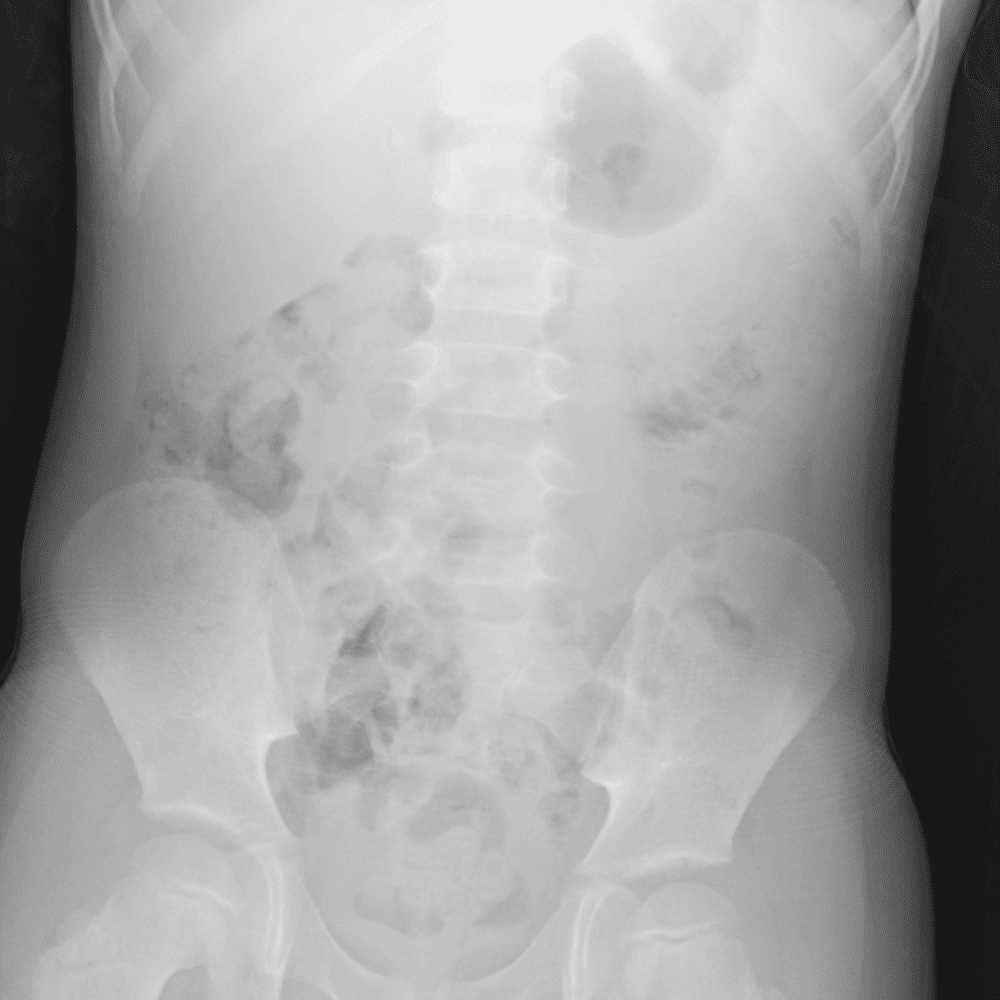

Peds Abdomen

Practice

Simulates call by including subtle or difficult cases and some normals.

30 cases